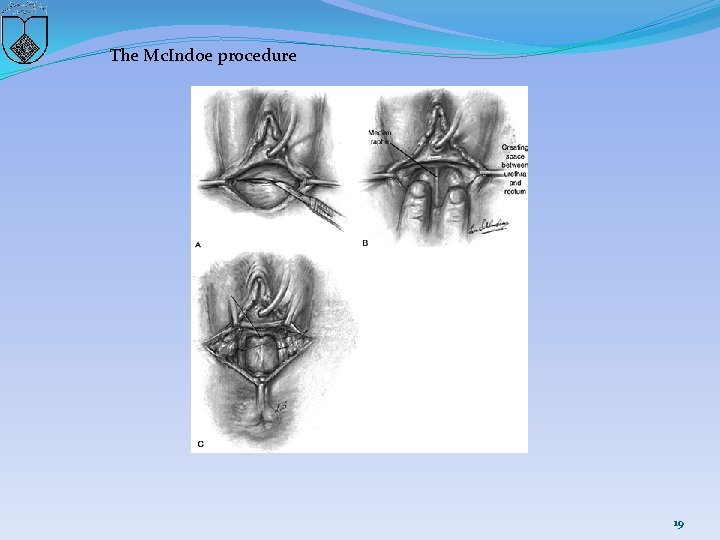

The Mc. Indoe procedure 19